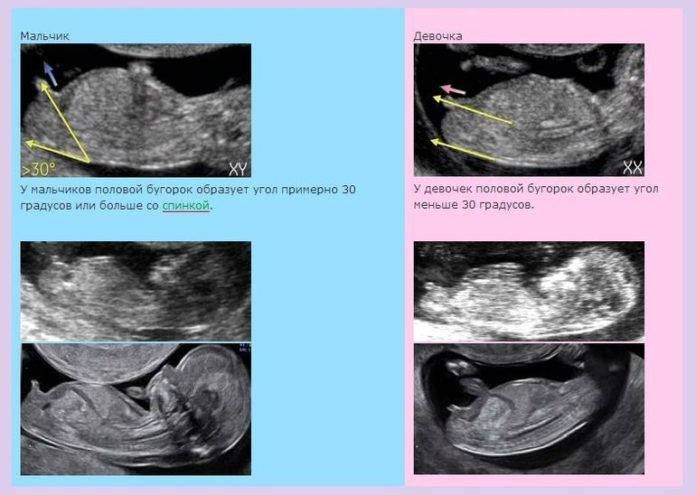

Девочка, половой бугорок параллельно в телу. Ни на одном фото мальчиком не выглядит. Снизу на таком сроке неинформативно смотреть, только сбоку.

На третьей фотке с наклейкой-это вид снизу, со стороны попы? Если да, то это девочка. Хотя я бы гендер пати до 20ти недель делать не стала, не надежно это😬 мне до 20ти недель даже смотреть пол отказывались на узи, а в 20 там уже 100% точно можно определить